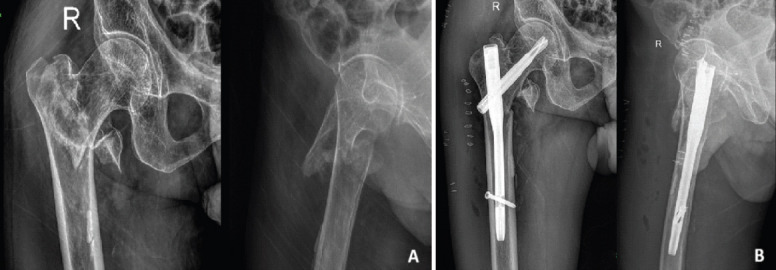

Introduction: Intertrochanteric fractures are one of the most common osteoporotic fractures in the elderly population. Most of them are managed with surgical fixation using proximal femoral nails. We report a patient with pseudoaneurysm of the profunda femoris artery following surgical fixation of an intertrochanteric fracture, which is a very rare complication.

Case report: An 80-year-old male patient presented 3 weeks post-surgical fixation for an intertrochanteric fracture with pain and swelling of the thigh. Radiological evaluation revealed a pseudoaneurysm of the profunda femoris artery, which was managed by the cardiothoracic and vascular surgery team.